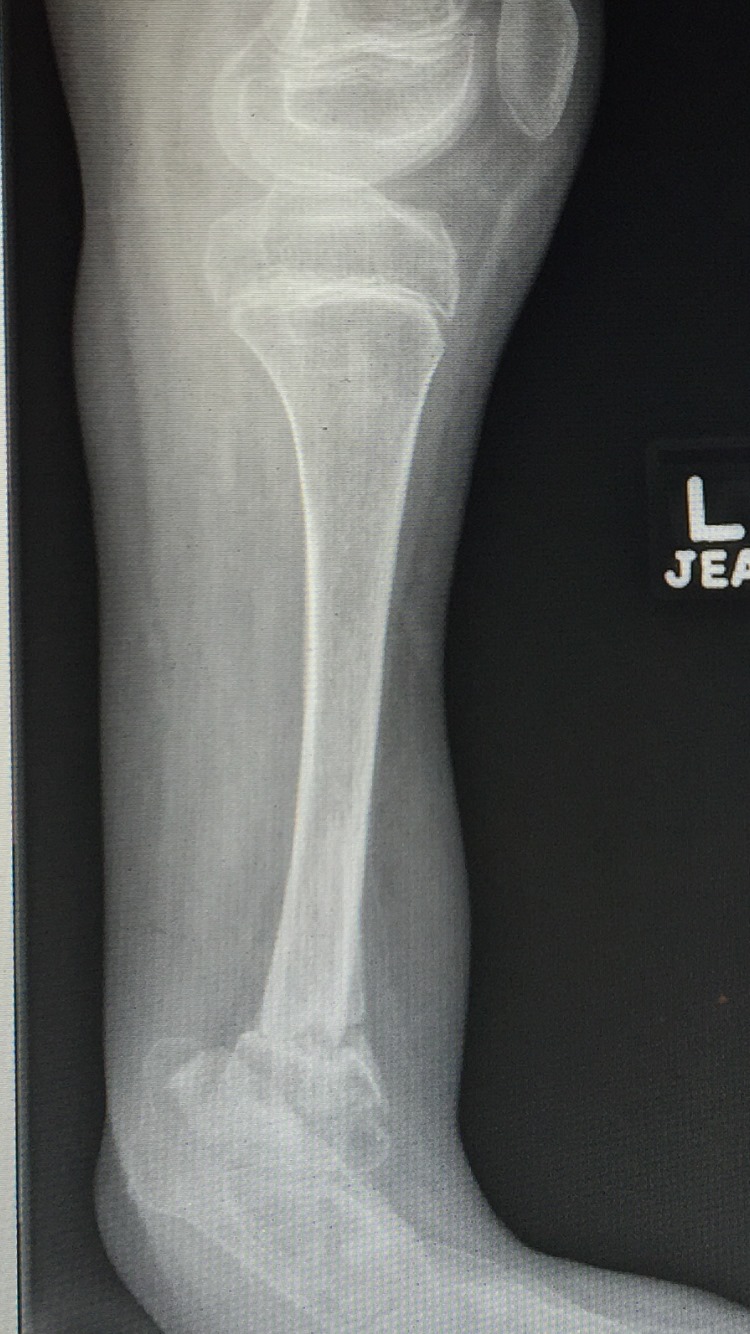

Ausencia congenita del peroné

A los papás de Lazarito les dijeron en Estados Unidos que la única alternativa para su hijo era una amputación; buscando segundas opiniones, llegaron conmigo. Lazarito, de 13 años, tiene #hemimelia #perónea, una ausencia congénita del peroné que causa malformaciones y acortamientos. Para evitar la amputación, se le realizó una reconstrucción del tobillo y alineamos su pierna de forma funcional. Ahora, mi pacientito ya camina con apoyo al 100%, realiza sus actividades diarias y dice que empezará a jugar fútbol. Agradezco a sus papás por la confianza y a sus familiares en Guadalajara por recomendarlo conmigo.